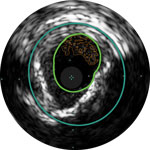

Lumen

Exzentrische fibröse Plaque mit tiefliegendem Calcium

Schallschatten

Erleichtert die Dimensionierung des Geräts, um eine präzise Wandapposition, Medikamentengabe und Platzierung sicherzustellen

Verstehen Sie Art und Schweregrad der Plaque, um das richtige Gerät zu wählen

Visualisieren Sie die Position der Plaque für eine präzise Behandlung

Bestätigen Sie die Position des wahren Lumens oder des subintimalen Führungsdrahts